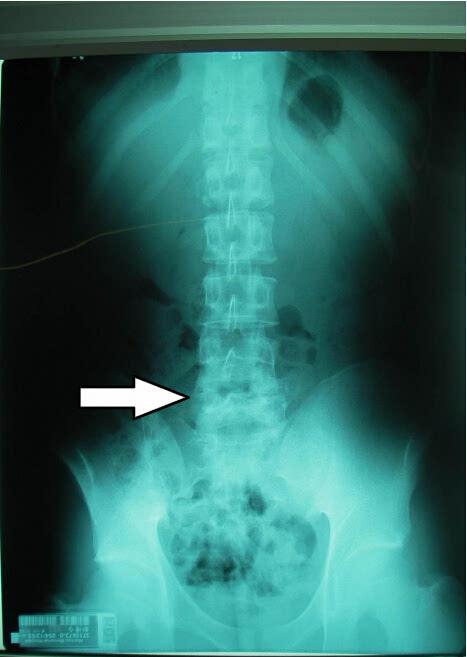

鉴于这种情况,目前在世界上许多发达国家,已经逐渐摈弃既有的关节疗法,普遍采用纯天然锯峰齿鲛软骨粉用于临床治疗,并且取得了临床上的纤维环软骨再生的验证。它为人们彻底克服强直性脊柱炎带来明亮的曙光。现在,在欧美日等为中心的国家中,已经形成了世界性的关节代替疗法的巨大潮流,在欧洲一些国家,已把纯天然锯峰齿鲛软骨粉萃取物认定为药品,日本也选定了企业专门提供临床之用。但是,因为选材困难,加工讲究,而价格稍微昂贵。你可以查查看,然后根据自己的病情和经济条件调整用量,一段时间后到医院确认脊椎软骨恢复的情况,祝早日彻底康复!强直性脊柱炎是一种血清反应阴性,病因不明的常见关节疾病.因为目前对此病还没有太好的办法根治,需要坚持进行功能锻炼,包括游泳,打太极拳,做广播体操等.但不提倡进行篮球,足球,网球等较为剧烈的运动.通过正确的锻炼,可以有效地增加脊柱活动度,改善脊柱功能,控制病情发展,你好,强直性脊柱炎是一种慢性全身性炎性疾病,它的病因不明,主要侵犯脊椎,尤以骶髂关节病变最为常见。它的最为显著的变化为关节的纤维化和骨性强直。建议尽早去正规专业医院进行检查和综合性治疗,控制病情不发展,保护关节脊柱。

强直性脊柱炎是中医的五劳七伤,它的性质是进行性疾病,它的性质可以导致椎体周围韧带纤维化,骨上软骨膨胀。而腰椎间盘突出是劳损病症,是因为髓核受到挤压溢出纤维环压迫椎管神经形成的。有强直性脊柱炎的人很少有可能患腰椎间盘突出,只是X光显影的误导和CT的误导才有此说法。我建议你看一看中医强直性脊柱炎教纲和中医腰椎间盘突出诊疗教纲。由于一些医务人员对强直性脊柱炎的早期表现的认识不清楚,当强直性脊柱炎出现腰痛症状时,首先考虑的是腰间盘突出症。

椎间盘突出症是一种常见病,正常人群的检出率很高,病没有腰椎疼痛症状。当腰椎出现疼痛症状,结合腰椎影像学检查,误诊为腰间盘突出症。但是,腰椎间盘突出症的治疗方法与强直性脊柱炎明显不同,许多强直性脊柱炎患者按椎间盘突出症治疗无效,医生往往不认为是诊断问题,而错误地认为是难治的椎间盘突出症。因此,强直性脊柱炎与腰间盘突出症的混淆是导致强直性脊柱炎误诊的重要原因之一。

强直性脊柱炎与腰间盘突出症的不同点,在发病年龄上强直性脊柱炎是14-45岁,而椎间盘突出症一般在20岁以上。强直性脊柱炎有全身症状在急性期有发热,疲乏,关节肿胀,多处疼痛伴随关节加纳供应,无放射疼痛症状,而椎间盘突出症是腰部局部疼痛,有神经放射症状,并且这种疼痛与腰椎活动度有关系等。